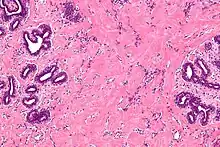

High magnification micrograph of pseudoangiomatous stromal hyperplasia showing the characteristic small, anastomosing blood vessel-like channels. H&E stain. | |

Pseudoangiomatous stromal hyperplasia (PASH) is an overgrowth of myofibroblastic cells in the breast. It has an appearance similar to fibroadenomatoid changes.[1]